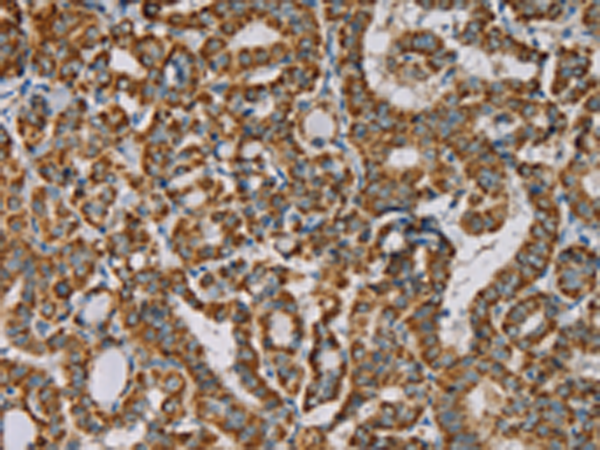

分类: 科研抗体货号: P08468别名: NP; HNP; NRPN; PRSS19; TADG14应用: IHC反应种属: Human